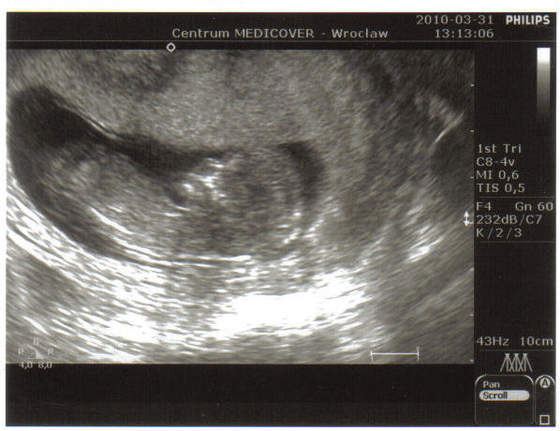

A to moje dzieciątko 11t3d, leży główką do dołu więc obróciłam zdjęcie bo tak lepiej się patrzy:

Kopia Zdjęcia z t&#.jpg